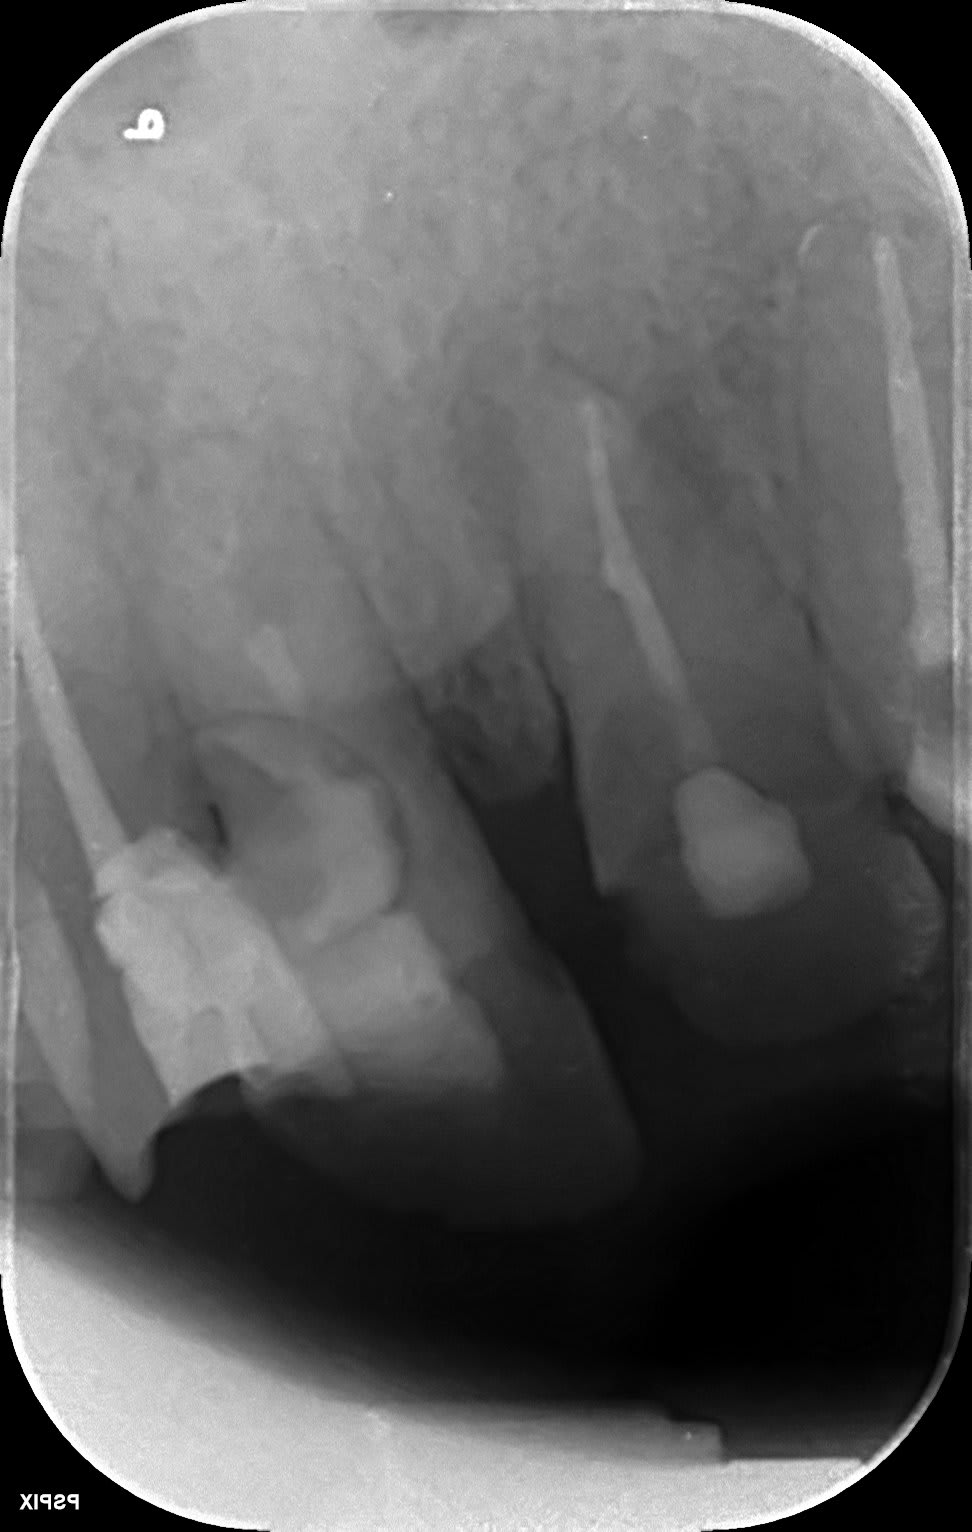

Un petit cas traité il y a 2 ans. La résorption s'étendait jusqu'à la limite du tiers apical et entourait complétement le canal.

Aux dernière nouvelles la dent est toujours là.

(Le point de départ est disto palatin, donc dur dur d'avoir une super belle limite pour l'obturation de la résorption)